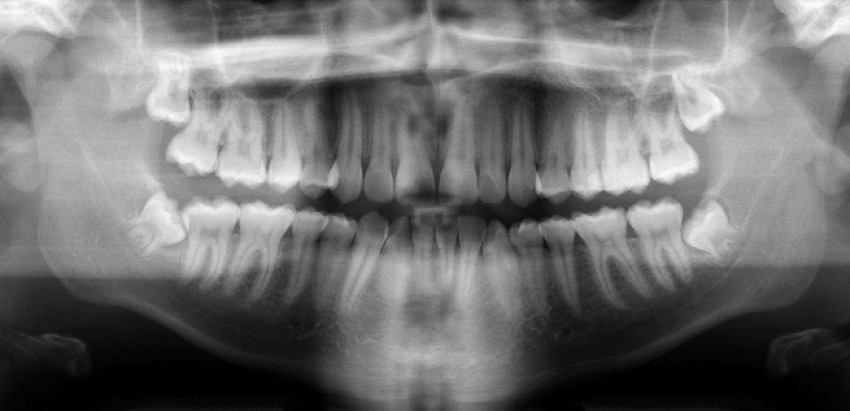

Răng khôn mọc lệchHình ảnh 1 (đa số các trường hợp).

Bạn có thể thấy răng khôn mọc ở dưới nằm nghiêng và kẹt (hình 1), xung quanh có một quầng sáng nhỏ là biểu hiện của một biến chứng nguy hiểm tiềm tàng. Dựa vào chân răng khôn, nha sĩ cũng có thể đoán được bệnh nhân này còn rất trẻ (khoảng 16-18 tuổi), và thời điểm nhổ răng khôn lý tưởng nhất là khi chân răng của bạn đã hình thành khoảng một nửa đến 2/3. Căn cứ vào hình ảnh Xquang, những chiếc răng khôn cần phải được loại bỏ ngay và lúc này là thời điểm hoàn hảo để làm điều đó.